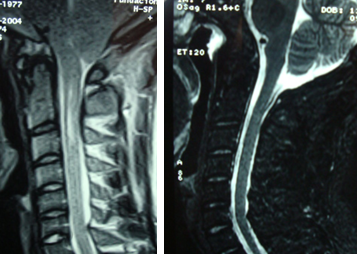

Resonancia magnética pre y postoperatoria mostrando la ampliación de la fosa posterior.

El síndrome de Chiari I se caracteriza por el descenso de las amígdalas cerebelosas por el foramen magno hacia el canal espinal.  El Chiari II (protrusión de amígadals cerebelosas, vermis y parte del IV ventrículo y bulbo medular) está asociado a los defectos de cierre del canal espinal lumbosacro (mielomeningoceles) y tiene un cuadro clínico y resolución distinto. Las teorías que explican el desarrollo del Chiari I son básicamente la teoría hidrodinámica de Gardner basada en el desarrollo de una fosa posterior más pequeña  y la teoría de la disociación cráneo espinal que se basa en una diferencia de presión entre el endocráneo y el canal espinal, lo que favorecería el descenso de las amígdalas cerebelosas. Independientemente de la causa, el Chiari I se caracteriza por la protrusión de las amígdalas cerebelosas hacia el canal espinal. Un descenso< a 5 mm suele ser considerado como variante anatómica. Los descensos mayores pueden generar síntomas y requerir tratamiento quirúrgico. La compresión crónica de la unión bulbomedular puede obstruir la circulación de LCR y generar siringomielia de la médula. En estos casos, el tratamiento quirúrgico inicial requiere la corrección del Chiari y si después de un lapso de tiempo prudencial, la siringomielia no mejora puede requerir tratamiento quirúrgico de la misma.

El tratamiento quirúrgico del Chiari I se realiza en pacientes sintomáticos y consiste básicamente en la descompresión y ampliación quirúrgica de la unión cráneo cervical. Esto incluye la craniectomía suboccipital con o sin apertura de la primera vértebra cervical y la adición de una plástica de duramadre que permite aumentar el volumen de la fosa posterior y la normal restitución del pasaje de LCR. La ecografía intraoperatoria permite  detectar aquellos casos donde la descompresión óse sola alcanza como tratamiento qurúrgico.